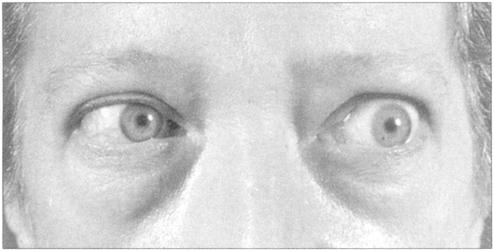

甲亢突眼症(图229);Addison’s病(图230);肢端肥大症(图231);

图229 甲亢突眼症